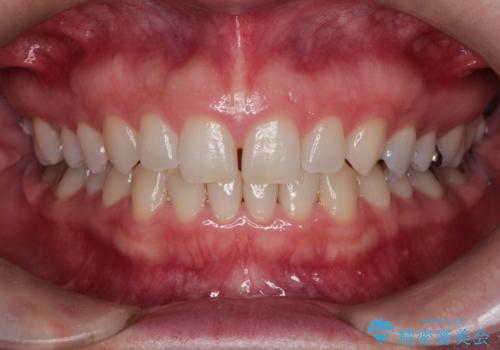

前歯のデコボコした歯並びをマウスピースで改善!

- 前歯の歯並びの改善を希望され来院された患者様です。

初診時の歯並びの状態としては、下顎に中等度のがたつき(叢生)がある状態でした。

抜歯は行わず下顎の奥のスペースを利用して歯をスライドする方法の他に親知らずの抜歯そして上下ともに歯列弓の拡大やディスキング(歯と歯の間の隙間を作る処置)を行い叢生を改善しました。

歯の大きさの不揃いが原因の正中のズレは、ディスキング量を調整することで合わせました。

矯正装置としてはマウスピースを使用しています。

見た目、嚙み合わせ及び、治療期間や施術内容に大変ご満足いただきました。